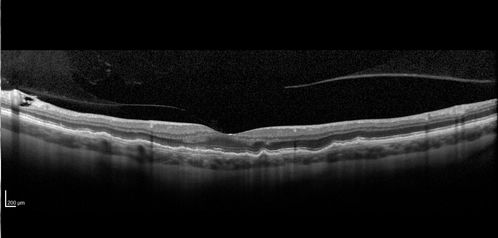

Late Onset Retinal Degeneration (L-ORD)

55 year old with acute vision loss from a CNVM in the right eye. He responded to Lucentis therapy. His mother and her family has been confirmed genetically to have L-ORD and were part of the early reports.